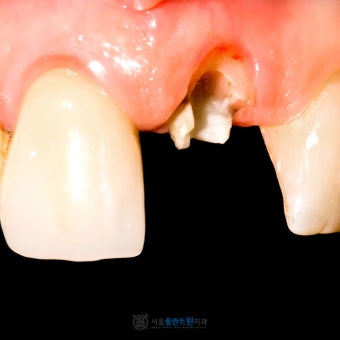

크게 깨진 경우

- 씹을 때 통증

- 찬물, 뜨거운 음식에 민감

- 피가 나거나 이빨 속이 보임

겉으로 보기엔 비슷해 보여도, 속까지 손상됐는지 여부가 정말 중요해요.